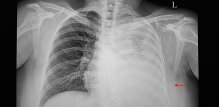

Voda u plućima ili pleuralni izljev Što se događa u tijelu kad se tekućina počne nakupljati